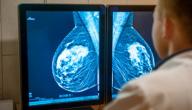

يكون الورم خبيثًا (سرطانيًا) إذا كانت خلاياه تهاجم الأنسجة المحيطة أو تنتشر إلى أعضاء الجسم الأخرى، ولحسن الحظ معظم الكتل التي تصيب الثدي هي أورام حميدة وليست سرطانيةً؛ إذ لا تنتشر إلى أعضاء الجسم الأخرى ولا تشكّل تهديدًا على الحياة، ويصيب سرطان الثدي النساء عادةً ويمكن أن يصيب الرجال أيضًا، كما أن معظم أنواع سرطانات الثدي تكوّن كتلًا محسوسةً داخله، لكن يمكن كشفها في مراحل مبكرة جدًا عن طريق فحص الماموغرام الذي يكشف الورم مهما كان صغيرًا قبل أن يكوّن كتلةً محسوسةً داخل الثدي وقبل ظهور أيّ أعراض. ومن الجدير بالذكر أن الرضاعة الطبيعية -خاصةً لمدّة تزيد عن السنة- تقلّل من احتمال الإصابة بسرطان الثدي؛ لأنها بعد الحمل تقلل من مستويات الإستروجين.[١]

• الأشعة السينية: إذا شعرت المرأة بأعراض سرطان الثدي يجب استشارة الطبيب للبدء بإجراء تصوير بالأشعة السينية، وهو فحص بموجات الماموجرام لتصوير الثدي، ويمكن أن يقترح الطبيب التصوير بالموجات فوق الصوتية التي تعد أكثر دقّةً من الأشعة السينية؛ لأنّها قد تُظهر الكتل والتشوّهات الموجودة في الثدي، وتكشف ما إن كانت الكتلة صلبةً أو سائلةً.[٦]